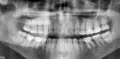

• Необходим рентгеновский снимок данного зуба, после данного исследования специалист определит причину возникновения боли. Если в данном зубе не был удален сосудисто-нервный пучок, возможно понадобится данная процедура. Все дальнейшие манипуляции определяются специалистом после осмотра и проведения диагностических манипуляций.